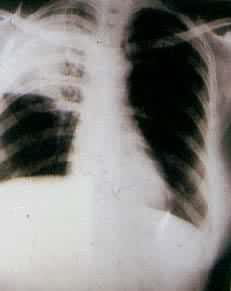

肺部疾病(一) 肺部疾病(二) 大叶肺炎 小叶肺炎 间质性肺炎 肺脓肿(正位) 肺脓肿(侧位) 支气管扩张 浸润性肺结核

肺结核空洞 肺不张